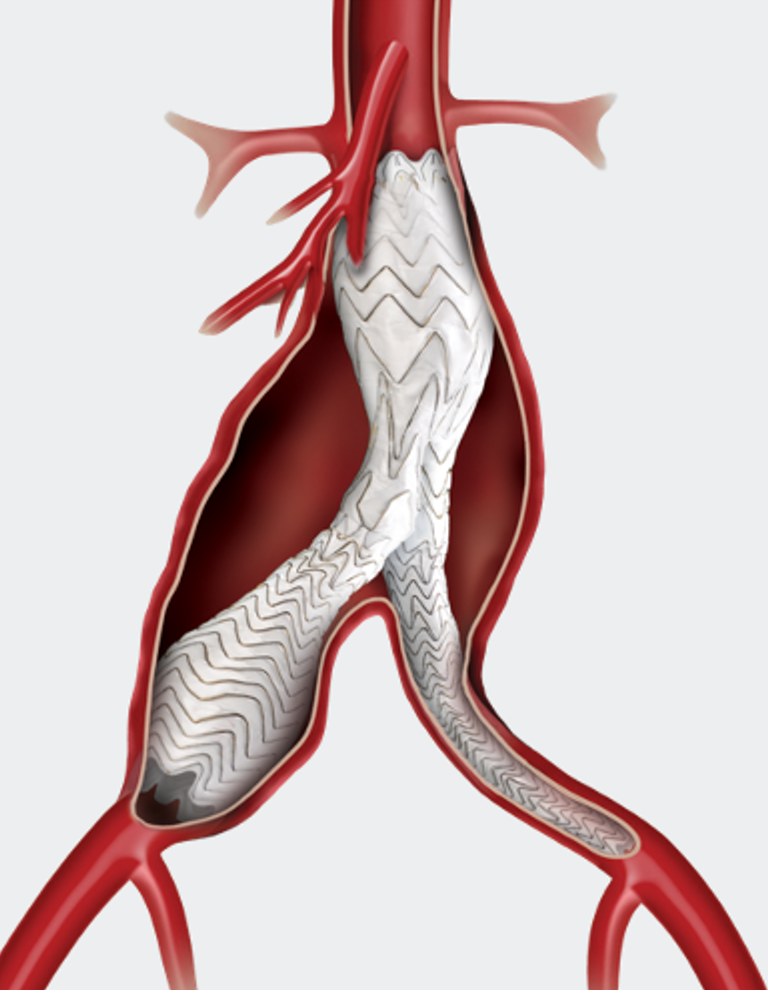

平行支架腔内技术

适应证:髂总动脉直径>15mm ,上肢入路良好(无严重血管扭曲或闭塞)。

操作要点:双支架平行植入髂总动脉 ,技术成功率88%-100% ,但6个月通畅率88%。

优势:操作相对简单 ,符合血流动力学;

风险:存在Gutter内漏、支架挤压闭塞风险 ,且依赖上肢入路 ,可能引发血栓脱落、卒中并发症。